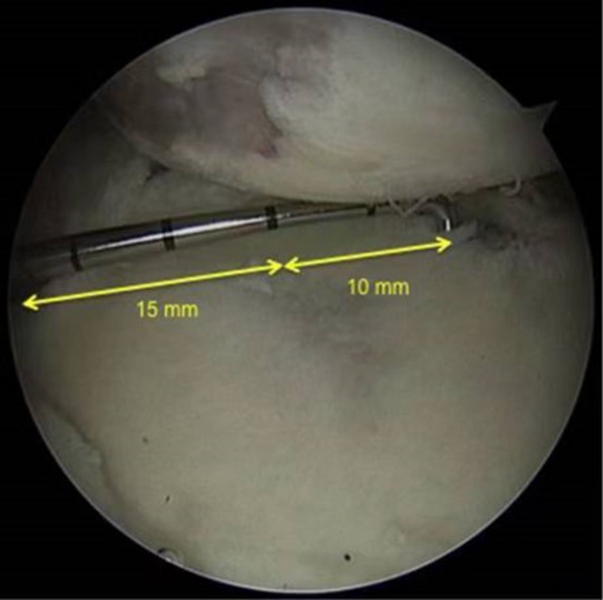

图32 Hill-Sachs损伤测量方式

上图为Hill-Sachs损伤的测量方式,采用前端为4mm的探钩,可以看到Hill-Sachs损伤的区域为3个探钩前端的跨度,因此HS为12mm。

评估报告提示:肩胛盂轨迹(Glenoid Track,GT)19.9mm,Hill-Sachs间距(Hill-Sachs Interval,HSI)24mm。

图34  BB=12

骨桥宽度的测量方式,采用前端为4mm宽的探钩测量,发现骨桥宽度正好为3个探钩前端的跨度,应为12mm。

计算Hill-Sachs间距(Hill-Sachs Interval,HIS)。这个间距应为Hill-Sachs损伤的宽度(HS)加上骨桥(Hill-Sachs损伤的外侧缘到肩袖止点)的宽度(BB),HSI:HS+BB=24mm。